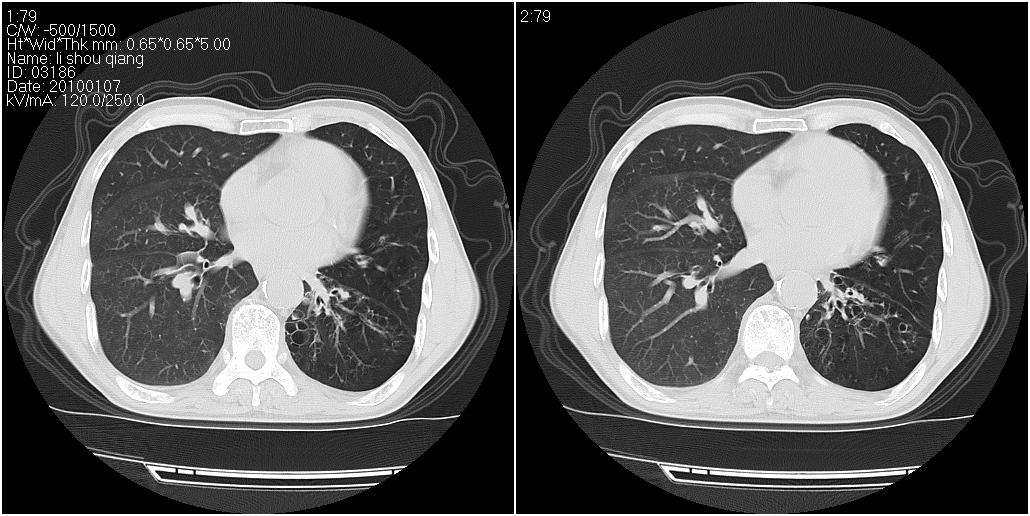

标题: CT24038:男性,58岁。主因咳嗽带血性CT检查。 [打印本页]

标题: CT24038:男性,58岁。主因咳嗽带血性CT检查。

右肺中叶外侧段见一不规则的软组织肿块,边缘可见毛刺,并见厚壁空洞,与胸膜分界欠清。另左下肺见多个小囊状扩张区